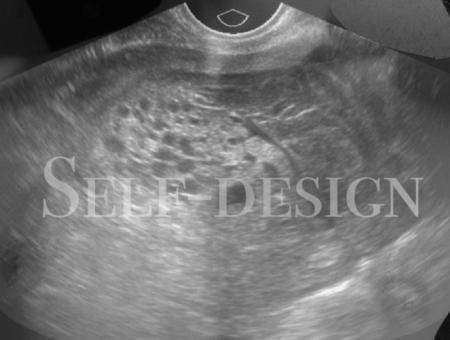

In the film Catalysis I investigate new relationships between nature and machine by converting 2D CT scans (Computer Tomography) into 3D ceramic prints. Now that artificial body parts can be cultivated in laboratories, the perception of the body in general, and of organs in particular, is changing. The importance of machines in health care will change drastically in the coming decades. In my research, cyborg, the cybernetic organism, plays a key role, in which the cyborg is considered a hybrid machine and organism in one. The cyborg is a model for the mechanical expansion and metamorphosis of nature in the human body.

The film Cyber Story – Inner Body is a journey through my body, made with CT and MRI scans. The film is a first resultof a two year project Nature / Databody.During the project research I collaborated with scientists from the Neuro-imaging Center and the Institute of Diagnostic Radiology of the Technical University Dresden (TU Dresden) specializing in CT scans and ultra-sound.

2019C.Rockefeller Center Dresden, Duitsland During the Nature- / Databody research project I collaborated with scientists from the Neuro-imaging Center and the Institute of Diagnostic Radiology of the Technical University Dresden (TU Dresden) specializing in CT scans and ultra-sound. With this technique I was able to make scans of multiple body parts, including my organs and brain. www.crockefeller.org/